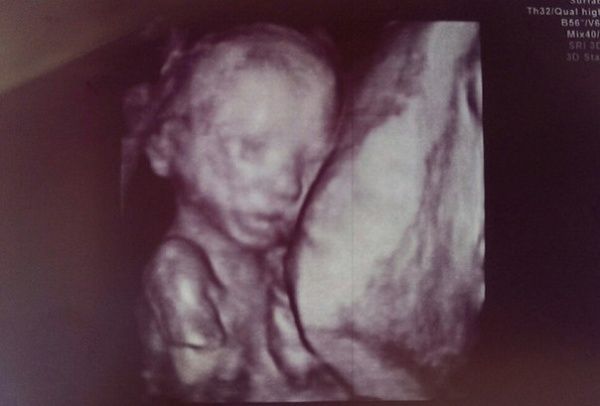

Починається 19 тиждень вагітності: що відбувається з малюком і мамою фото і опис, здатні багато чого пояснити. По акушерським розрахунками, термін відповідає 21 тижню. Всі органи і системи в тілі маленької людини вже повністю сформовані, але їх повноцінна самостійна робота ще неможлива. Але завдяки істотного прогресу в галузі медицини, плід, який народився на такому маленькому терміні має високі шанси на виживання.

Як змінюється малюк? На цей момент внутрішньоутробний розвиток плода: опис та фото дозволяють зрозуміти, що всередині людина, хоч і нагадує поки ще велику ляльку. Пропорції його тіла вже строго дотримані і аналогічними показниками новонародженого. Шкіра дитини до кінця тижня практично не просвічується.

Зріст і вага дитини з цього терміну почнуть інтенсивно збільшуватися, а на даному етапі вони складають 25 – 28 см і 340 – 400 р. відповідно. У тому випадку, коли вагітність багатоплідна, вага кожного плоду на цьому тижні рідко перевищує показник в 370 р. Зростання при цьому залишається на тому ж рівні, що і в «одинаків».